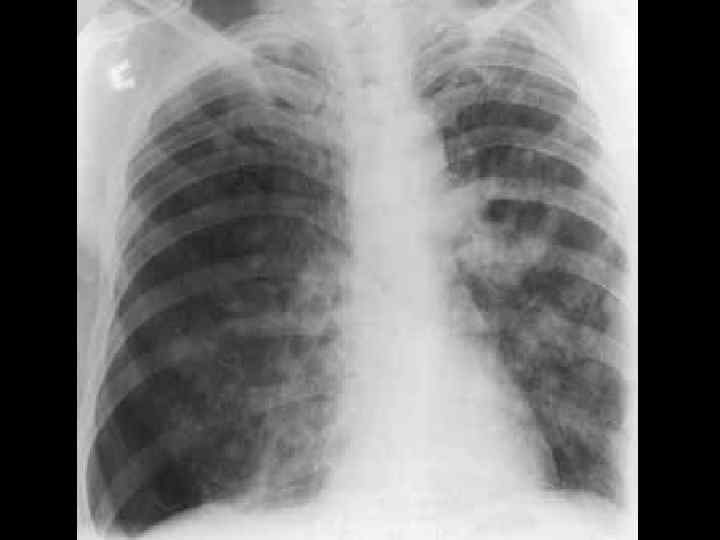

ОБТУРАЦИОННАЯ ТОЛСТОКИШЕЧНАЯ НЕПРОХОДИМОСТЬ • • опухолевый анамнез возраст больных схваткообразные боли в животе задержка стула и газов "поздняя" рвота вздутие живота интоксикация Симптомы Цеге–Мантейфеля, Обуховской больницы • при рентгенографии- множественные толсто- и тонкокишечные уровни, пневматоз толстой кишки